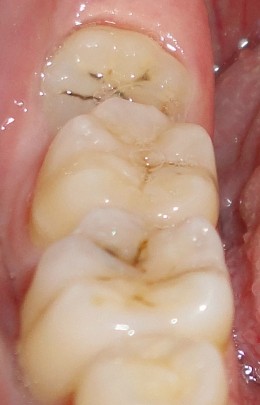

1 、智齿有蛀牙的情况:

如果智齿出现了蛀牙的情况的话,是要马上拔除的,智齿是一个比较容易发生蛀牙的部位,主要是其位置比较靠近里面,我们平时刷牙很难清洁到的缘故,所以容易产生蛀牙。